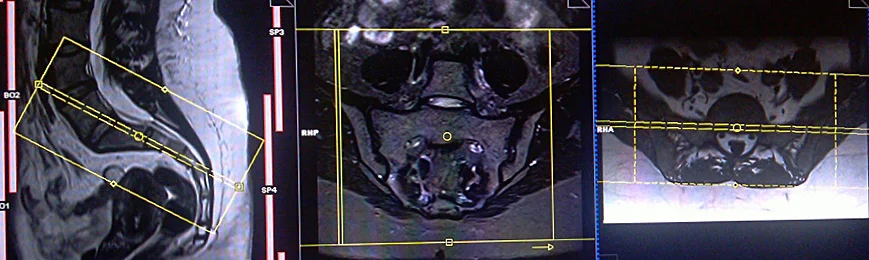

CASE STUDY NO.1

Coronal planning

Axial planning